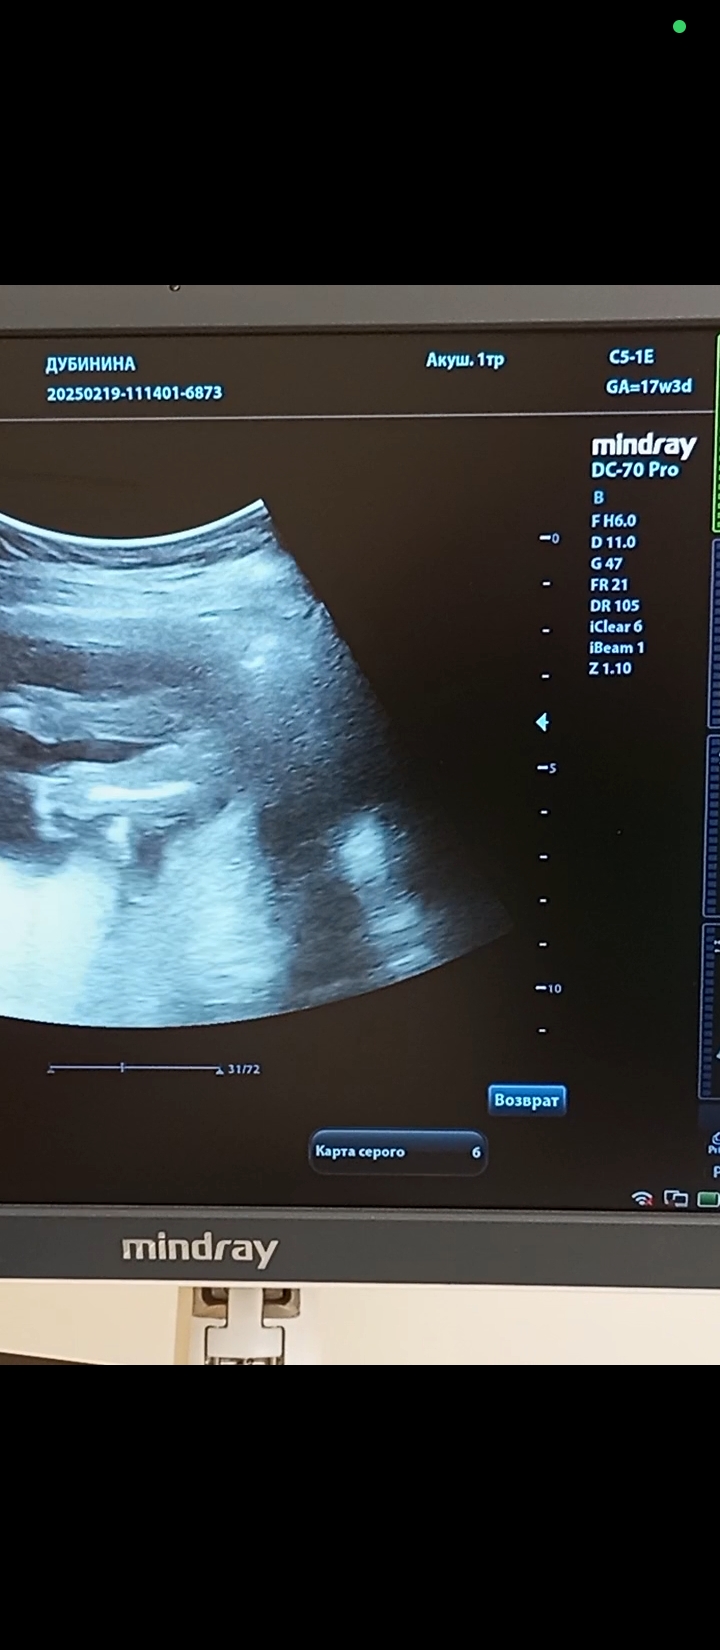

Валентина в Благополучная беременность 9 месяцев Пол Пол малыша Пол на 17 недели. Кто там? Посмотрите еще 20 записей на эту тему Отменить Ответить Ирина Лапина Мальчик🙂 27.02.2025 Ответить Чашка утреннего кофе Мальчик - мошонку видно, у девочек такого нет)) 27.02.2025 Ответить Валентина Чашка утреннего кофе, 27.02.2025 Ответить Виктория Я думаю девочка, у мальчиков сильнее торчит) 27.02.2025 Ответить Валентина Виктория, 27.02.2025 Ответить Виктория Валентина, девочка) 27.02.2025 Ответить Tatiana И я за мальчика. 27.02.2025 Ответить Ornella Mutit Предположу мальчика🩵 27.02.2025 Ответить Mari Я думаю мальчишка) у моей на таком же фото ничего не было между ножек) . 27.02.2025 Ответить Валентина Mari, здесь тоже ничего нет 27.02.2025 Ответить Mari Валентина, значит на том фото показалось) мелкое очень. Теперь вижу, что ничего нет) ну значит, девочка☺ 27.02.2025 Ответить Виктория Я за девочку 27.02.2025 Ответить Юля А мне кажется что мальчик ... 27.02.2025 Ответить Татьяна Мне кажется девочка 😁 У моего на такой фотке прям торчал корнишон😆 27.02.2025 Ответить Мальчик же? Пол мальчик или девочка? Чаты Беременных Выберите чат: Январята-2026 Февралята-2026 Мартята-2026 Апрелята-2026 Майчата-2026 Июнята-2026 Июлята-2026 Августята-2026